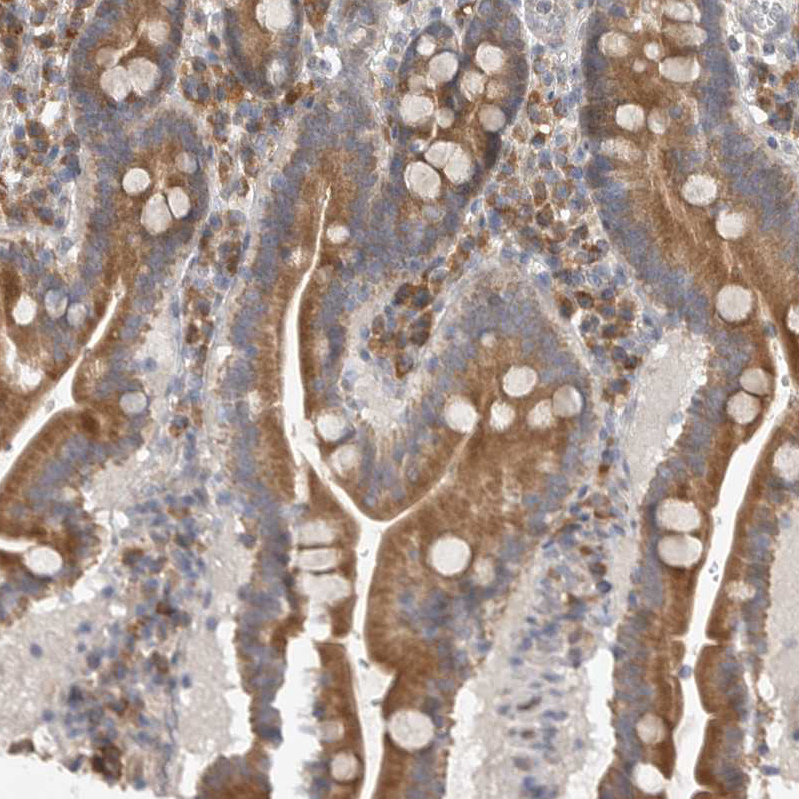

Immunohistochemical staining of human stomach shows moderate cytoplasmic positivity in glandular cells.